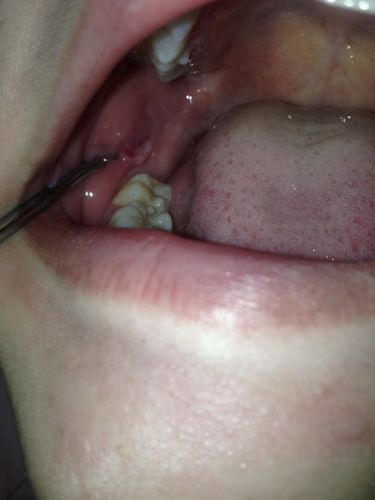

口腔溃疡处长小肉疙瘩是恶化了吗?

最常见的情况是,这个“小肉疙瘩”是溃疡愈合过程中的正常表现,但也可能是其他疾病的信号。

溃疡愈合期的“肉芽组织”(最常见)

这是最有可能的情况,通常无需过度担心。

- 成因:当口腔溃疡(特别是较深的溃疡)开始愈合时,身体会启动修复机制,在溃疡的基底,会生长出新的血管和结缔组织,形成粉红色或淡红色的、柔软的、微微隆起的“肉芽组织”,它的作用是填补溃疡缺损,为上皮细胞的生长提供“脚手架”。

- 特点:

- 颜色:粉红色或鲜红色,与周围黏膜颜色相似。

- 质地:柔软,触感不硬。

- 感觉:可能没有明显疼痛,或者只有轻微的触痛,原有的剧烈疼痛感已经减轻。

- 变化:随着时间推移,它会逐渐变平,最终被正常的口腔黏膜覆盖,完全愈合。